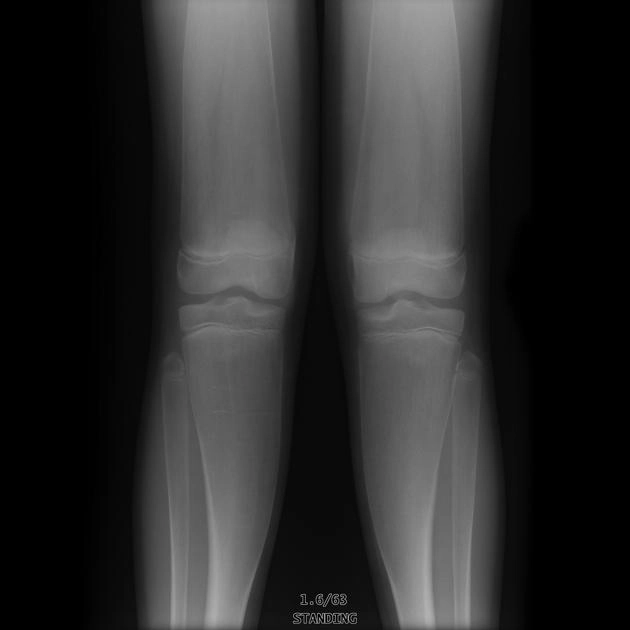

Loạn sản hành xương (Metaphyseal dysplasia)/ Bệnh Pyle

16/03/2026